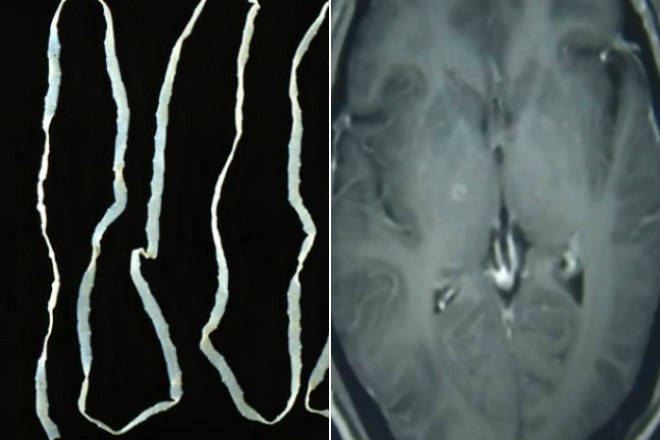

Um homem de 43 anos teve centenas de vermes retirados do cérebro e da região torácica em um hospital da província de Zhejiang, na China

Exames realizados no paciente mostraram que ele estava contaminado com o verme parasitário Taenia solium

Esse tipo de tênia, como também é chamada, é transmitida por meio da ingestão de carne de porco mal cozida

O médico Huang Jianrong explicou que as larvas do verme entraram no corpo de Zhongfa pelo sistema digestório e viajaram por meio da corrente sanguínea até alcançarem o cérebro

Ele foi diagnosticado com cisticercose (corpo) e neurocisticercose (cérebro) e recebeu medicamentos antiparasitário e outros com função de proteger os órgãos de demais danos

Jianrong informou que o paciente tem respondido bem ao tratamento, mas os efeitos da infestação maciça ainda não estão claros